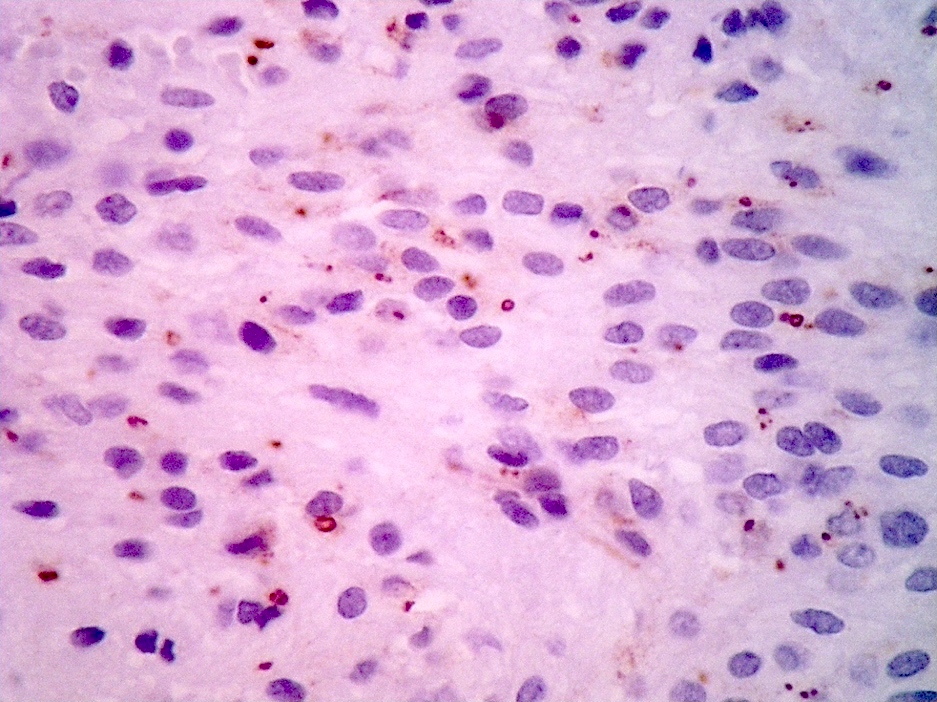

Positive stains

- Positive for S100, GFAP, vimentin

- Perinuclear dot-like pattern of EMA and D2-40 staining

- CD56 staining in lumina and tumor cells

- Variable membranous or dot-like staining for CD99

- Can have focal staining for keratin (CAM 5.2) and synaptophysin

- L1CAM can be positive in some supratentorial ependymomas but mostly is seen in RELA fusion tumors (Am J Surg Pathol 2019;43:56)

- In posterior fossa ependymomas, decreased expression of H3K27me3 is seen in posterior fossa group A, which has a worse prognosis (Acta Neuropathol 2017;134:705)